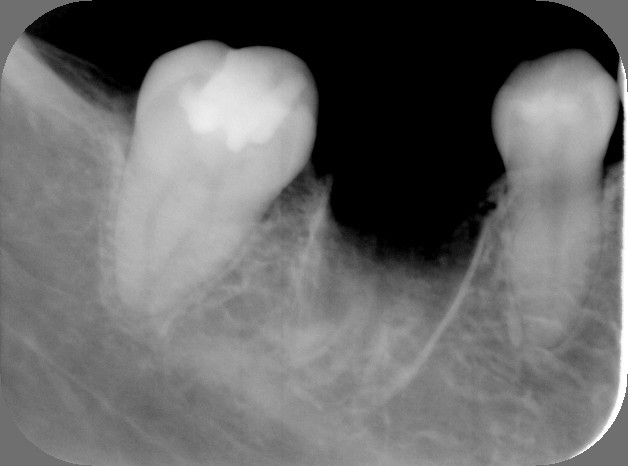

2.抜歯直後

3.上の親知らずを下へ移植直後